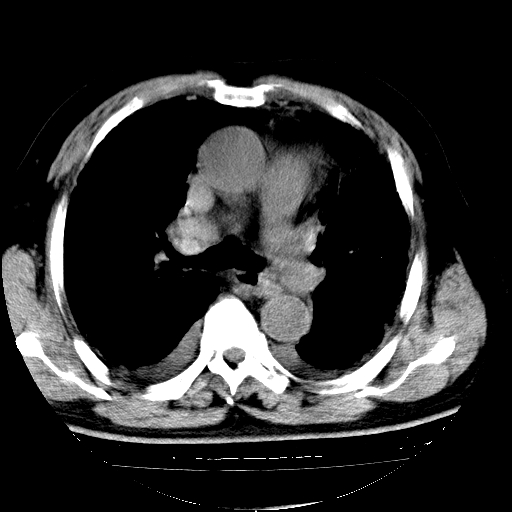

男,68岁,咳嗽、胸闷、发烧三天,查体:双肺散在湿罗音。

4.肺原性心脏病;

5.双侧胸腔少量积液;双侧胸膜增厚。

慢支合并感染.间质纤维化,心衰双侧少量胸腔积液

慢性支气管炎伴感染、肺气肿;间质性病变;双侧胸腔积液。

支持 慢支合并感染.间质纤维化,心衰双侧少量胸腔积液.